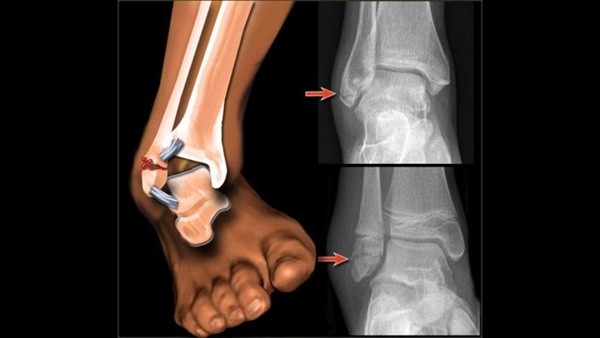

발목이 삐었다는 것은 인대가 손상된 것을 의미한다. 뼈와 뼈 사이의 간격이 비정상적으로 벌어지면 결과적으로 인대도 늘어나기 때문이다.

인대는 수백만 개의 인대섬유로 구성되어 있는데, 인대가 늘어난 다는 것은 인대섬유 중 일부가 손상되어 파열이 됐다는 뜻이다.

한편 높은 곳에서 뛰어내리거나 과격한 운동을 하다가 염좌가 발생한 경우에는 골절 유무도 확인해봐야 한다. 이를 위한 진단법으로는 오타와 룰(Ottawa rule)이 있다. 오타와 룰은 민감도 100%의 진단법으로 발목의 골절이 의심될 때 우선적으로 적용한다.

안과 바깥 복숭아뼈에서부터 위로 6cm까지, 새끼발가락에서 발목까지 이어지는 뼈(중족골 기저부), 발등에서 90도가 되는 부분의 앞쪽 튀어나온 뼈(주상골)을 눌렀을 때 통증이 심하거나 그로 인해 4보도 걷기 힘든 경우는 골절을 의심한다.

오타와룰에서 양성반응이 보이면 X-ray검사를 받아야 한다. 만약 골절이 확진되면 염좌에 해당하는 보존적 치료 외에도 골절을 치료하는 한약을 복용해야 한다. 환자의 상태와 체질에 따라 다르겠지만 보통 녹용, 보골지, 속단 등이 포함된 약이 처방된다.